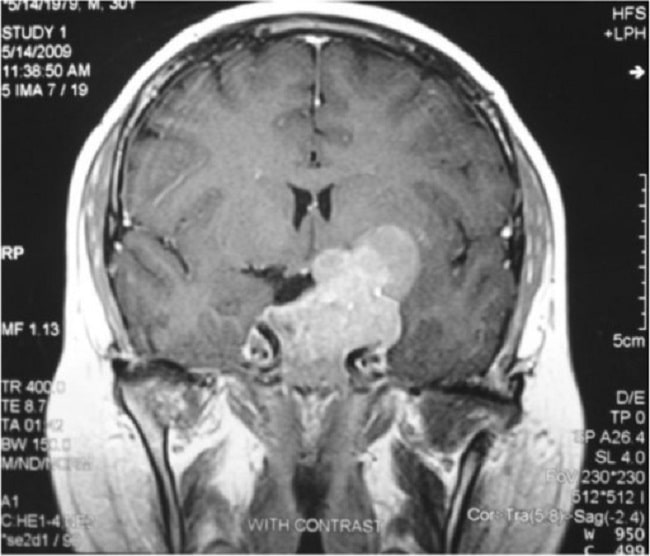

Gambar 1. CT Scan Prolaktinoma. Sumber: Openi, 2013.

Diagnosis prolaktinoma ditegakkan berdasarkan manifestasi klinis, peningkatan kadar prolaktin serum (> 150 ng/ml), dan gambaran tumor pada magnetic resonance imaging (MRI) atau CT scan. Anamnesis dan pemeriksaan fisik secara menyeluruh sangat diperlukan untuk mengidentifikasi efek massa tumor dan manifestasi hormonal, serta untuk menyingkirkan penyebab lain dari hiperprolaktinemia.[2,4]